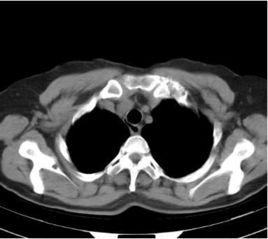

氣管支氣管憩室(tracheobronchial diverticula,TBD)是一種由於各種原因所致主要累及氣管和主支氣管,突出於氣管和支氣管腔外的囊性病變。